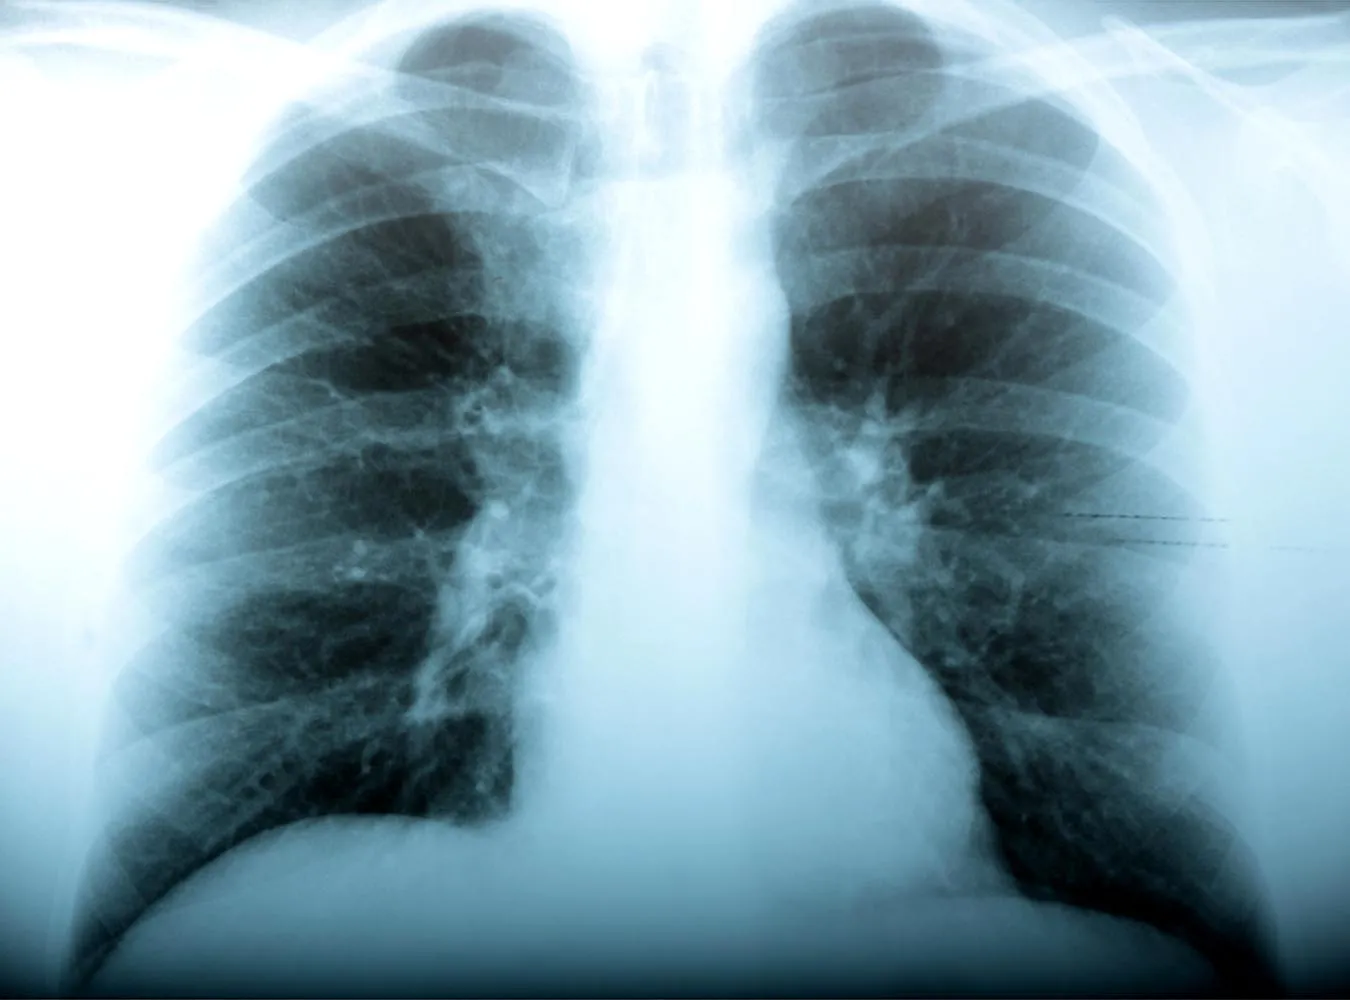

Potwierdzono już pierwszy przypadek śmierci chorego na świńską grypę w Polsce. To 37-letni pacjent z Gdańska. Tymczasem dramatyczne wieści dochodzą ze szpitala w Gorzowie Wielkopolskim. W ciężkim stanie leży tam 27-latek chory na grypę A/H1N1. Jest podłączony do respiratora.

27-letni gorzowianin . Obecnie przebywa na oddziale intensywnej ppieki medycznej. Ma problemy z oddychaniem, jest podłączony do respiratora. "Na razie trudno łączyć obecność tego wirusa z ciężkim stanem zdrowia pacjenta, " - przyznaje zastępca dyrektora Szpitala Wojewódzkiego w Gorzowie, Kamil Jakubowski.